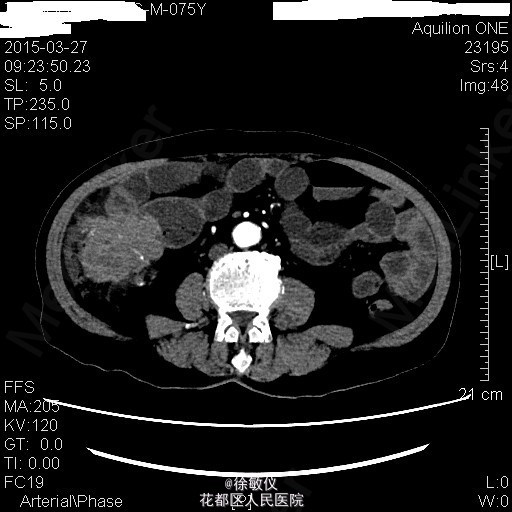

查体:生命体征平稳,贫血面容。腹软,全腹无压痛、反跳痛,右中腹可触及一大小约4*5cm包块,边界清晰,质稍硬。肝脾肋下未触及。 辅查:HGB 82g/L;CA19-9 625.97U/ml;CA-125 24.9U/ml;大便常规示:粪血红蛋白试验阳性。 全腹CT平扫+增强示:1、结肠肝曲及升结肠癌,浸润肠壁全层,周围多发淋巴结转移;2、直肠多发小息肉;直肠下段静脉曲张。